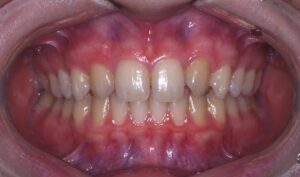

医院ブログ 2026/02/04

【表参道 歯科 審美歯科】顔貌との調和を考慮した前... こんにちは。表参道・青山にある歯科石上医院です。 先日、前歯部のセラミック…